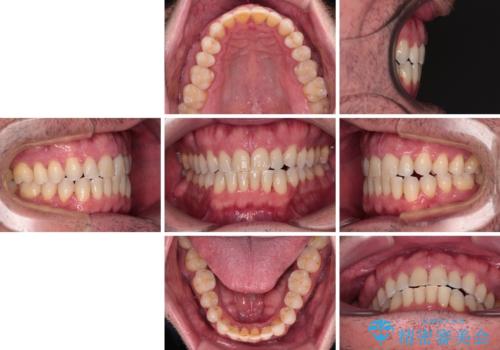

舌のトレーニング自体は簡単なものですが、無意識下でも舌が突出しないようにしなければならないため、毎日継続することが最大の難関です。

時間はかかりましたがトレーニングを頑張ってくださり、無事に前歯を接触させることができました。